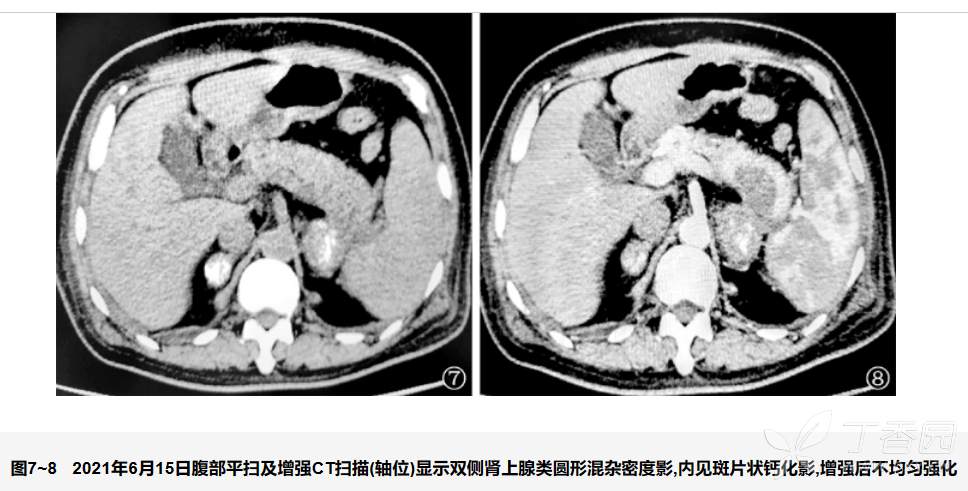

实验室检查:(1)皮质醇:0时为18.8 nmol/L,8时为17.6 nmol/L,16时为12.6 nmol/L;(2)促肾上腺皮质激素 (ACTH):0时为581.81 pg/ml,8时为645.3 pg/ml,16时为484.07 pg/ml (图5~6)。提示ACTH增高、皮质醇降低。腹部增强CT扫描显示:双侧肾上腺类圆形混杂密度影,考虑结核病变可能性大 (图7~8)。诊断:肾上腺结核,原发性肾上腺皮质功能减退,肾上腺危象。调整治疗,6月8日起给予糖皮质激素替代治疗,临床症状明显好转,血钠、血压改善明显 (图9~10)。

肾上腺结核CT扫描表现特点与病程密切相关,早期结核病病灶以炎症渗出及肉芽组织增生为主,表现为双侧肾上腺体积增大,而晚期多有典型的肾上腺萎缩、钙化。